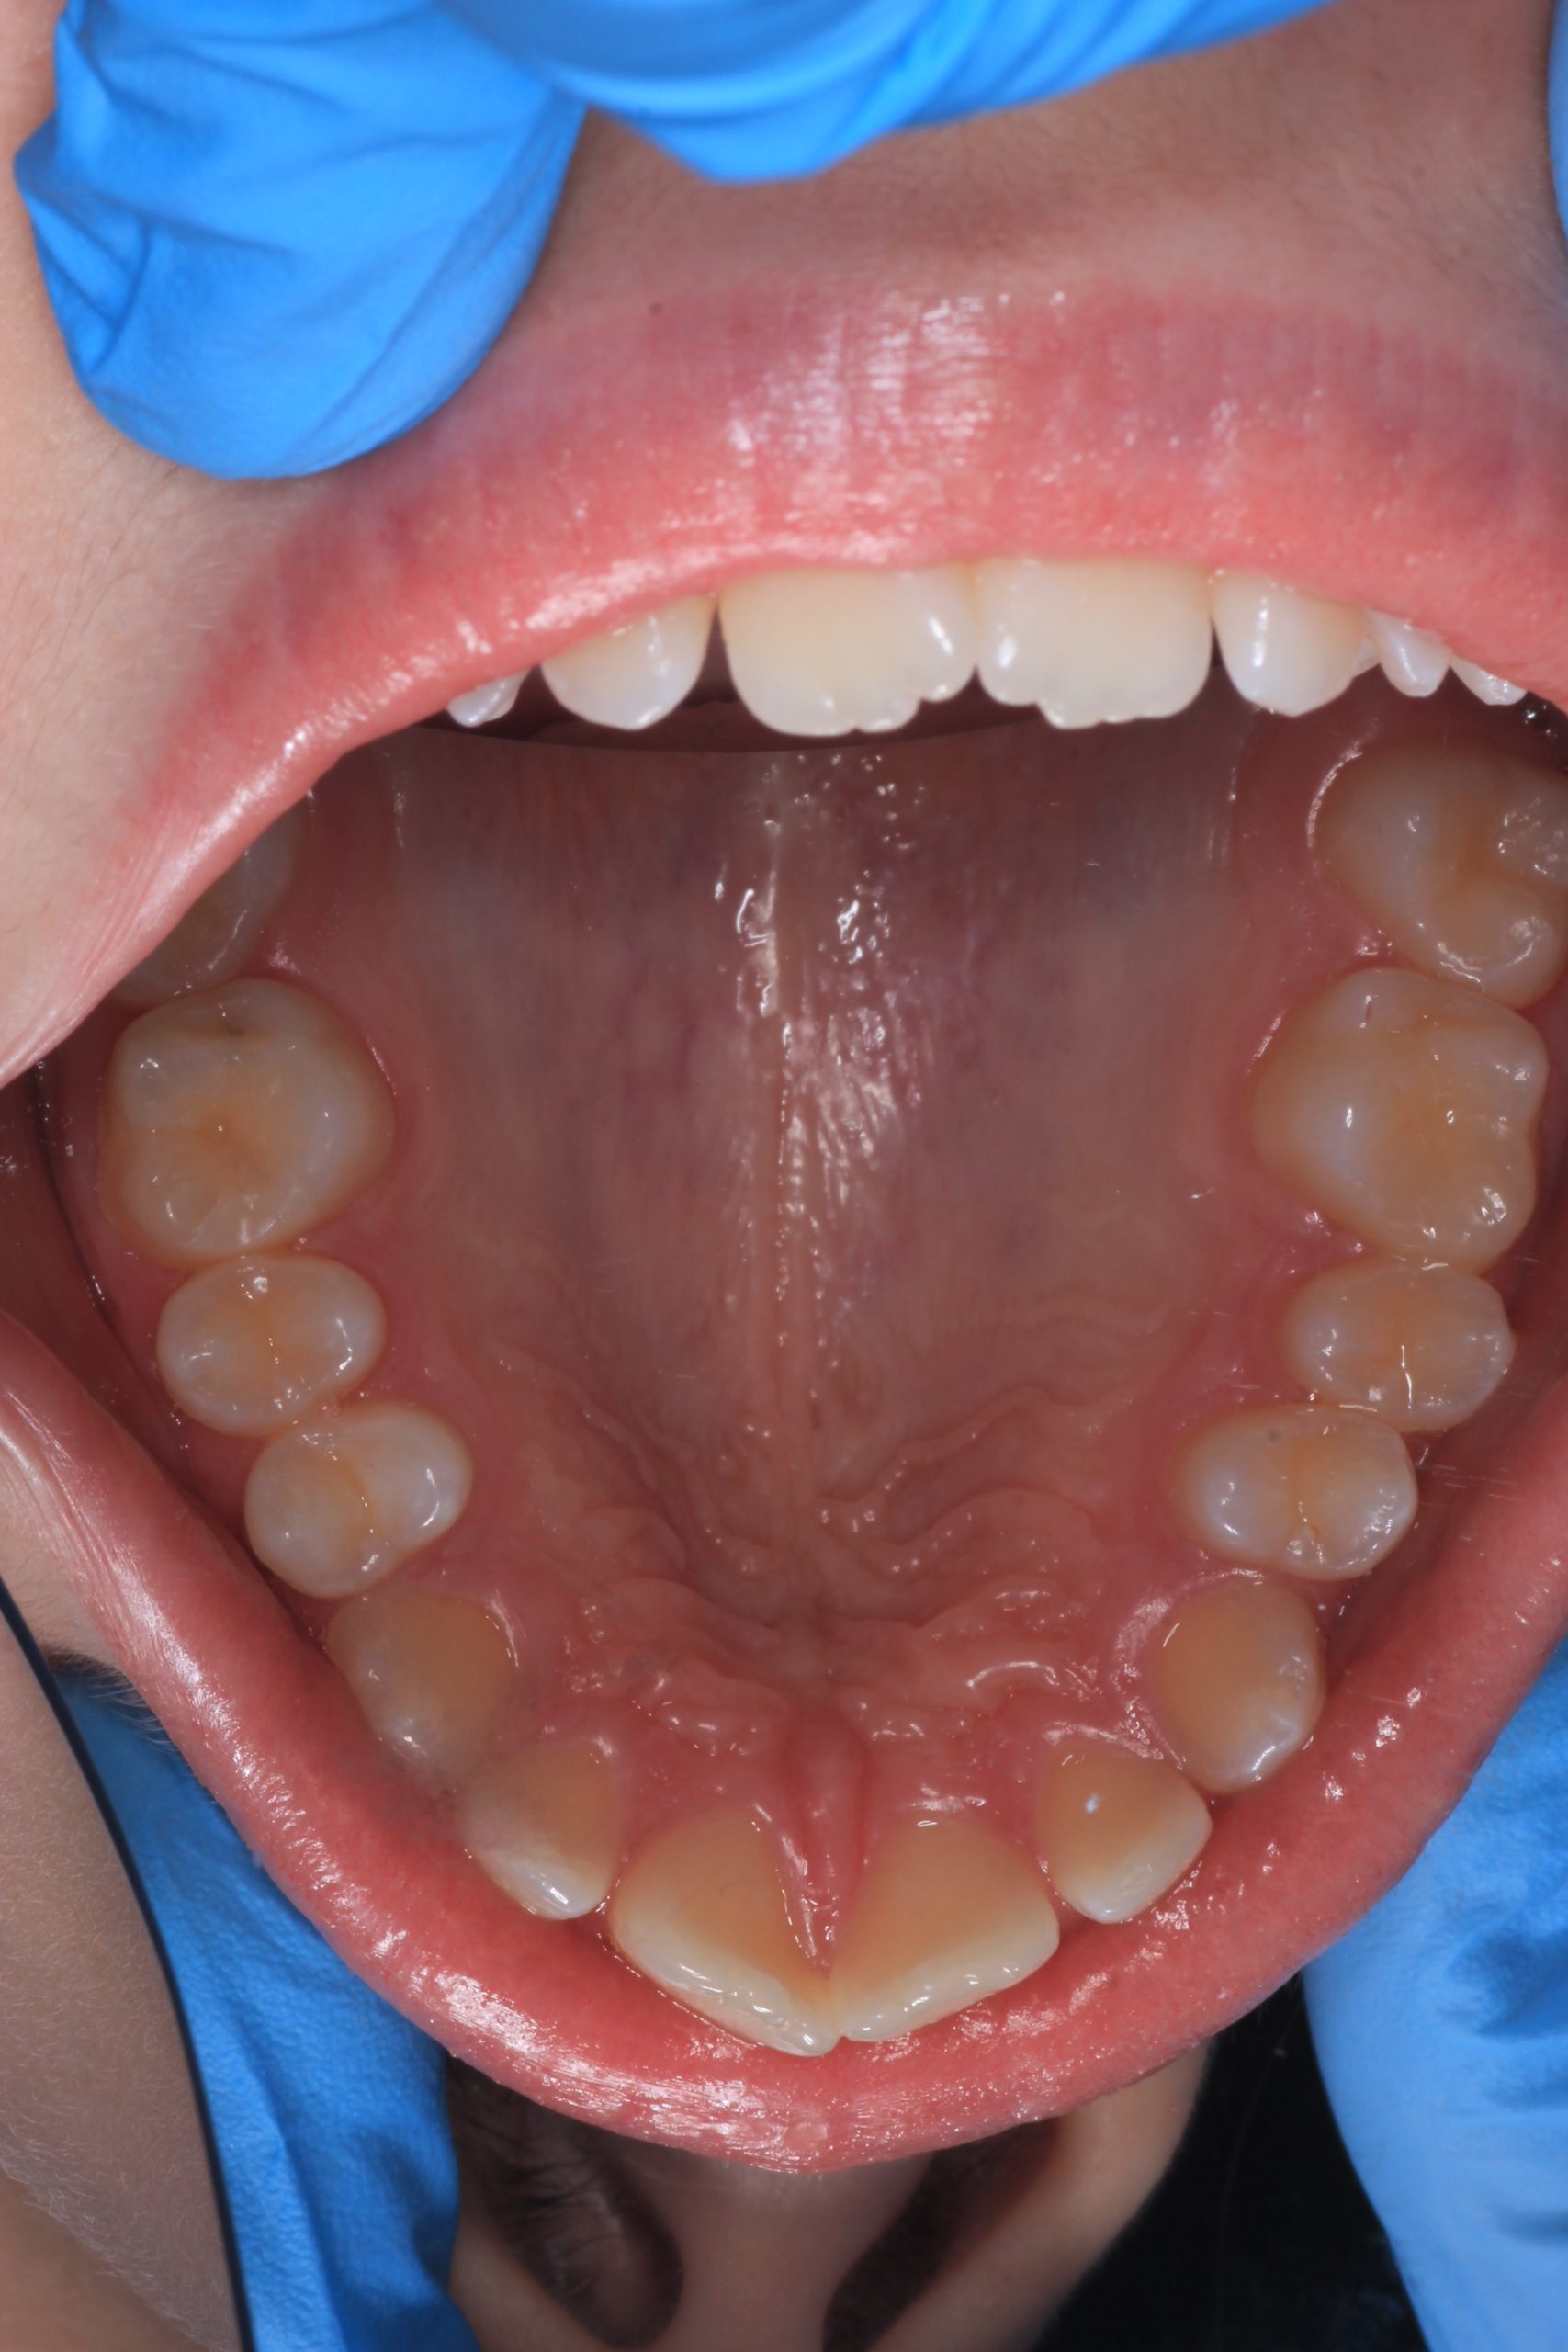

- Detailed Examination

We examine the condition of teeth, gums, and bite. - Plaque Disclosure with Special Indicators

From age 4–5 and up, we perform full GBT cleaning using an ultra-fine erythritol powder to clean even hard-to-reach areas gently and safely. It does not damage enamel and is ideal even around braces — no need to remove brackets or wires. - Tartar Removal (If Needed)

Any tartar is removed gently and painlessly. - Final Check-Up + Fluoride Protection